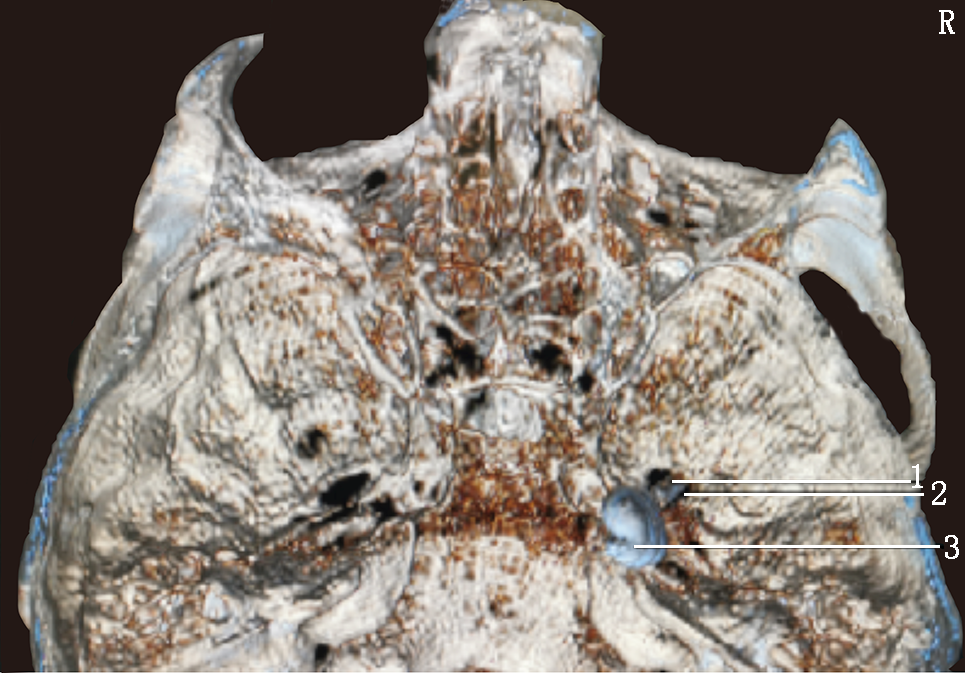

予以原方案继续口服镇痛药物,同时行眶上神经阻滞,利多卡因凝胶贴膏(北京泰德制药股份有限公司,国药准字H20180007,规格:700 mg)外贴,1贴/d,静脉抗生素抗感染、内分泌科会诊稳定血糖。入院调整3 d后,行局部麻醉下CT引导经皮穿刺半月神经节球囊压迫治疗(percutaneous microballoon compression,PMC)[3],因患者有强直性脊柱炎病史,不能平卧,予以多个体位垫辅助固定(图1),术前规划穿刺路径困难(图2)。按经典Hartel入路穿刺进入卵圆孔内口(图3A)[4],退出针芯,置入球囊导管,使远端Mark点与岩锥顶端平齐(图3B),注入30%碘海醇造影剂0.6 ml充盈球囊(图3C),球囊CT三维影像成“梨”形(图4),压迫半月节200 s,询问患者自诉右面部皮肤感觉轻度麻木,原疼痛基本消失,NRS评分2分,遂释放球囊内造影剂,拔出于球囊导管和穿刺针,结束手术。